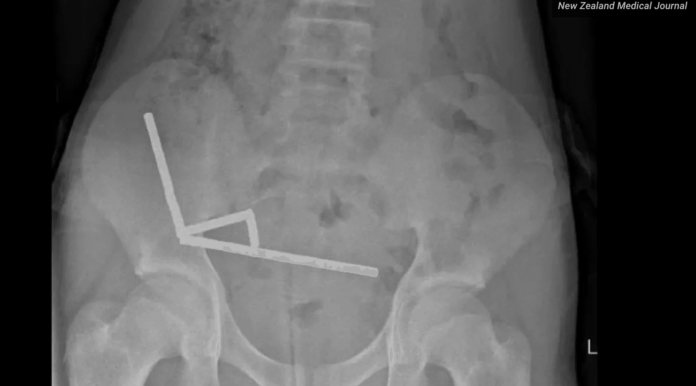

Lo que revelaron las radiografías y la operación de urgencia

Las radiografías mostraron una imagen muy clara y muy preocupante. En el interior del intestino aparecían varias líneas de pequeñas bolitas metálicas, agrupadas y pegadas entre sí. No estaban todas en el mismo tramo, pero la fuerza magnética las hacía atraerse, aunque hubiera paredes de intestino en medio.

Esa atracción tan fuerte hizo que diferentes partes del intestino se pegaran y se comprimieran. El tejido quedó atrapado entre los imanes y perdió riego sanguíneo. Los cirujanos describieron zonas con necrosis tanto en el intestino delgado como en el ciego, que es la primera parte del intestino grueso.